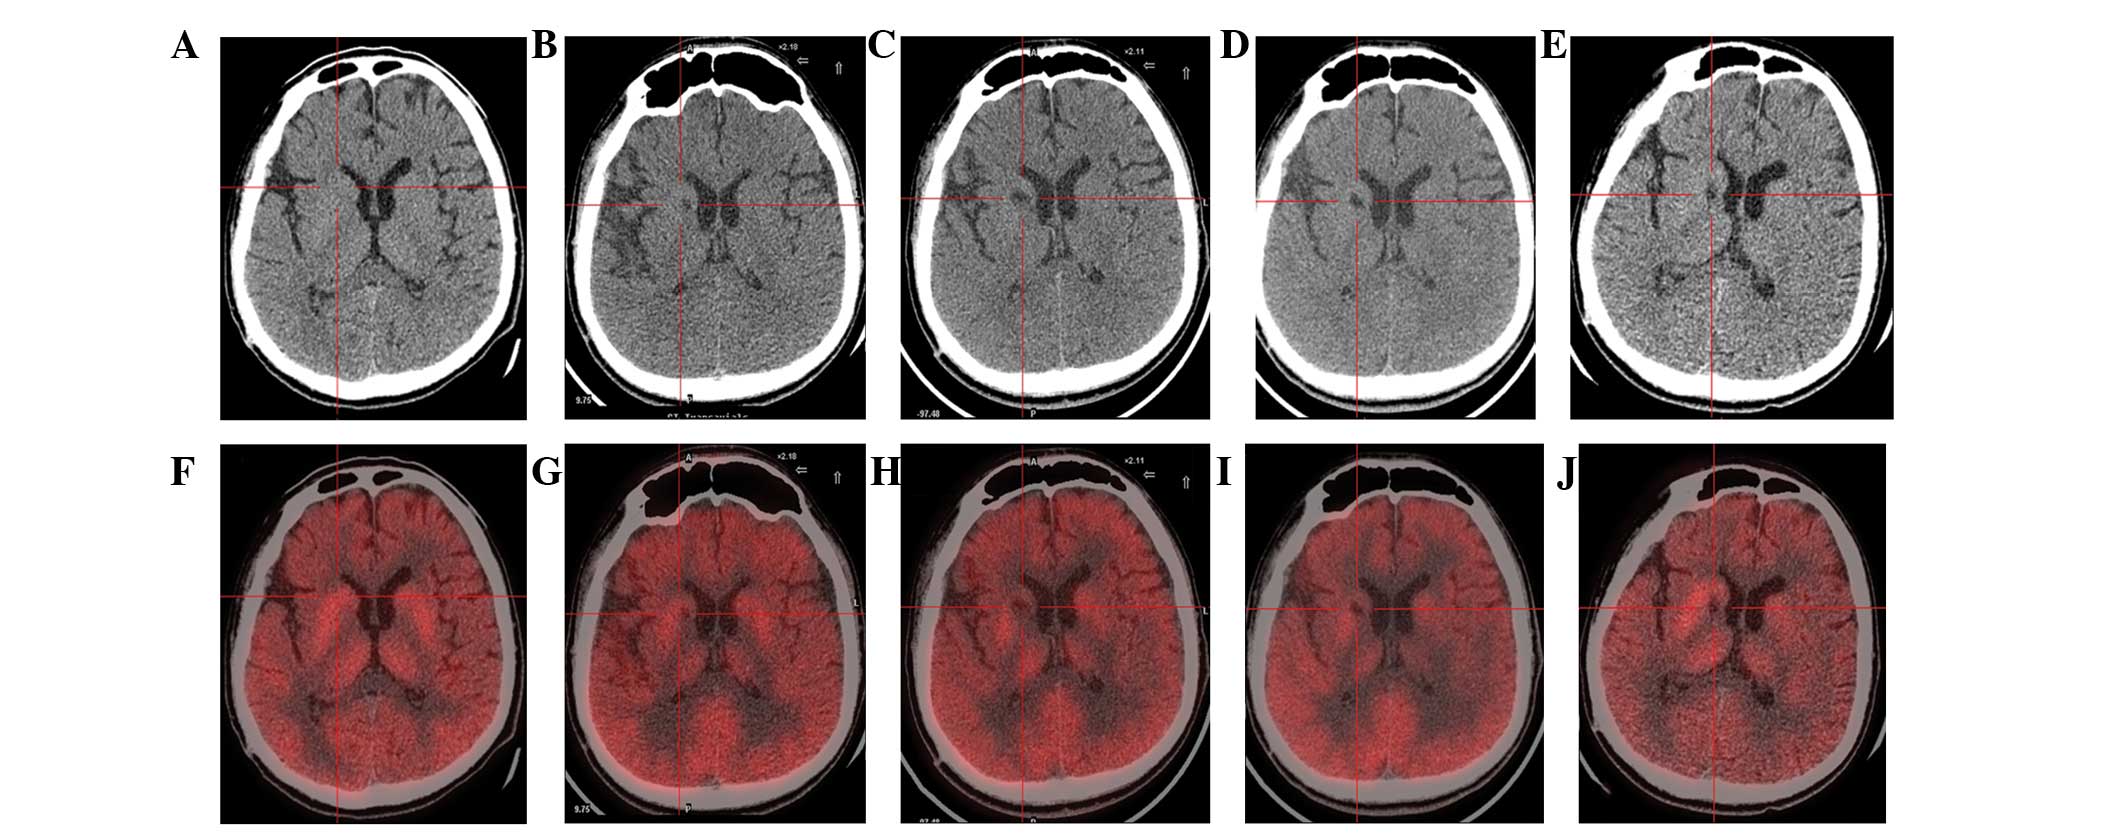

(A) 術(shù)前CT顯示腦萎縮。

(BE)術(shù)后1年、2年、3年、4年CT與術(shù)前相比均無明顯變化。

(F)術(shù)前18F-氟脫氧葡萄糖 (FDG) PET 掃描顯示,整個(gè)大腦皮層FDG攝取彌漫性減少,細(xì)胞核FDG攝取相對高于其他區(qū)域。術(shù)前1天,豆?fàn)詈撕颓鹉X的標(biāo)準(zhǔn)化攝取值 (SUV) 平均值/最大值分別為4.3/5.8和3.3/4.5。

(GJ) 神經(jīng)干細(xì)胞移植治療后分別 1、2、3 和 4 年的 18F-FDG PET 掃描顯示,雙側(cè)植入部位的豆?fàn)詈撕颓鹉X對 18F-FDG的攝取增加(紅十字)與植入前相同部位進(jìn)行比較。 豆?fàn)詈撕颓鹉X的SUV*平均值/最大值在 1、2、分別是術(shù)后3年和4年。 該結(jié)果表明移植后葡萄糖代謝比移植前稍高。

CT(圖1b-e)和MRI(圖2b-d)掃描顯示4年隨訪期間沒有顯著變化。 手術(shù)前1天(圖1f)和手術(shù)后1、2、3和4年(圖1g-j) 獲得18F-FDGPET掃描。術(shù)后雙側(cè)植入部位豆?fàn)詈撕颓鹉X18F-FDG攝取值較術(shù)前增加。這一結(jié)果表明,自移植以來,葡萄糖代謝逐年略有增加。